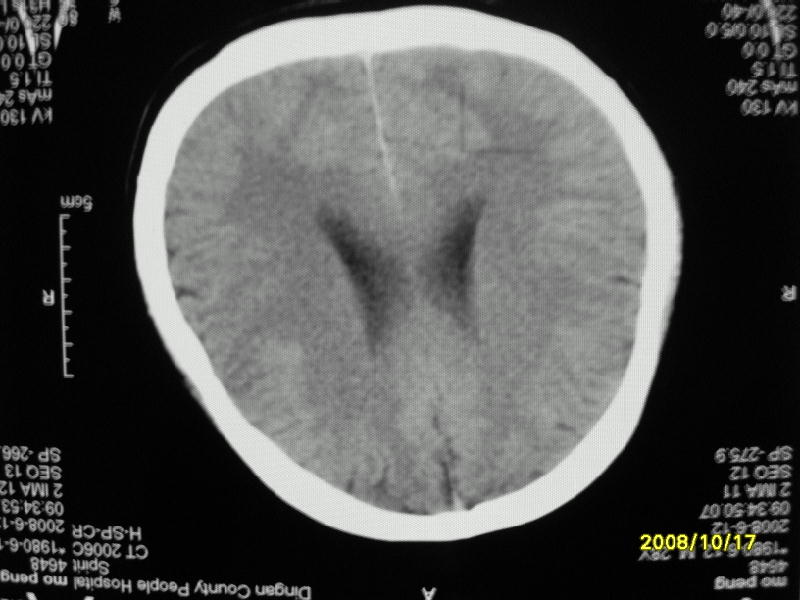

检查名称:     ct颅脑平扫           男     28岁

表现:左顶叶见斑点状致密影。边缘清,大小约0。3*1。0cm,余脑实质密度及灰白质结构示见异常。脑室系统大小,形态,密度未见异常。脑沟。脑裂。脑池未见异常密度影。中线结构无移位。

印象:左顶叶少许钙化灶

左顶叶见斑点状致密影。边缘清,大小约0。3*1。0cm,余脑实质密度及灰白质结构示见异常。脑室系统大小,形态,密度未见异常。脑沟。脑裂。脑池未见异常密度影。中线结构无移位。

印象:左顶叶少许钙化灶。

左顶叶见斑点状致密影